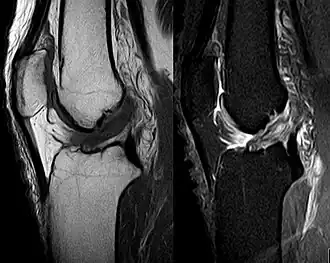

Medical imaging

Though clinical examination in experienced hands can be accurate, the diagnosis is usually confirmed by magnetic resonance imaging, which provides images of the soft tissues like ligaments and cartilage around the knee.[1] It may also permit visualization of other structures which may have been coincidentally involved, such as the menisci or collateral ligaments.[36] An x-ray may be performed in addition to evaluate whether one of the bones in the knee joint was broken during the injury.[9]

MRI is perhaps the most used technique for diagnosing the state of the ACL, but it is not always the most reliable technique as the ACL can seem healed on chronic cases with the proliferation of synovial scar tissue when treated conservatively.[37]

MRI is particularly useful in cases of partial tear of the ACL. The anteromedial band is most commonly injured compared to the posterolateral band.[38]